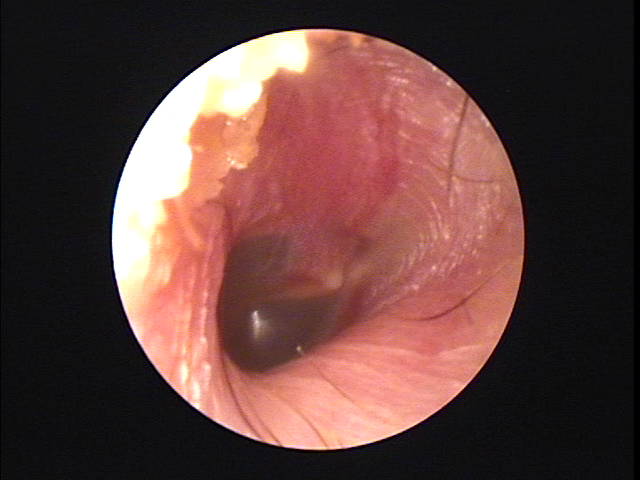

耳について | 千葉耳鼻咽喉科クリニック from chibacl.com